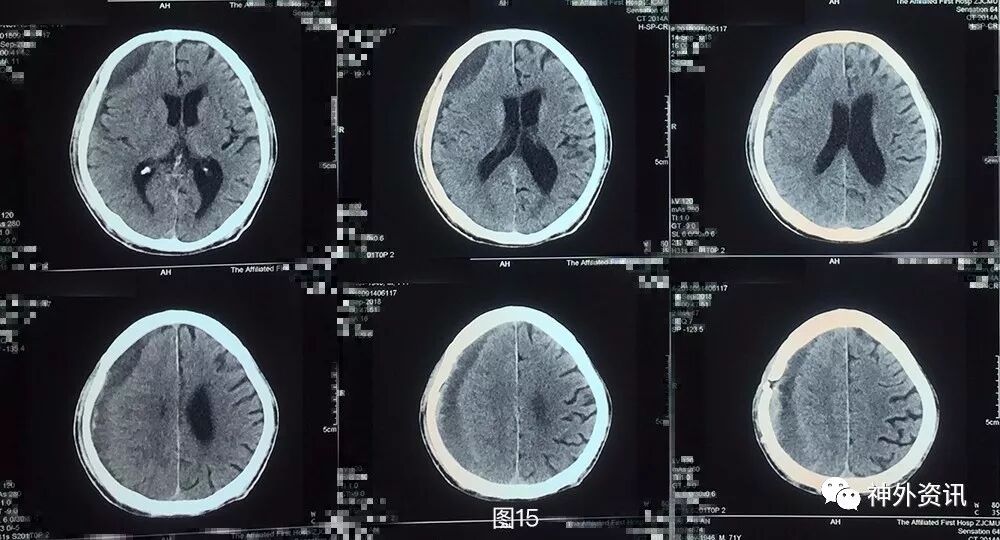

出院后患者分别于术后3周,术后5周复查头颅CT,提示血肿密度较前持续下降,中线偏移好转,占位效应较前有所缓解(图11)。

图11. 第三次术后3周,术后5周头颅CT,提示血肿密度较前持续下降,中线偏移好转,占位效应较前有所缓解。

目前患者查体神志清,精神可,GCS 15分,双侧瞳孔等大等圆,对光反应灵敏,心肺听诊无殊,腹软,无压痛反跳痛,左侧肢体肌5级—,右侧肢体肌力5级,病理征未引出。继续恢复中。

在其后的CT复查中,患者硬膜下血肿仍有增多趋势,但考虑到患者临床症状未出现进展,因此继续予以药物保守治疗。至出院时,患者临床症状已逐渐好转,神志转清,左侧肢体肌力恢复至3-4级,头颅CT结果显示颅内血肿密度逐渐下降,提示血肿逐渐液化,但血肿腔体积未见明显减小,占位效应并未消除。出院后患者定期复查头颅CT,至术后5周,患者头颅CT结果提示血肿密度较前持续下降,中线偏移好转,占位效应较前有所缓解。